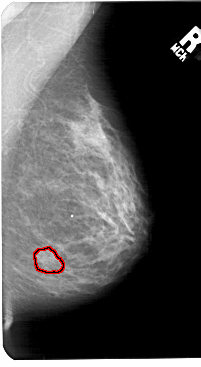

A_1569_1.LEFT_MLO

LEFT_MLO LINES 5491 PIXELS_PER_LINE 3646 BITS_PER_PIXEL 12 RESOLUTION 43.5 NON_OVERLAY

RIGHT_MLO LINES 5491 PIXELS_PER_LINE 3001 BITS_PER_PIXEL 12 RESOLUTION 43.5 OVERLAY

FILE: A_1569_1.RIGHT_MLO.OVERLAY

TOTAL_ABNORMALITIES 1

ABNORMALITY 1

LESION_TYPE MASS SHAPE IRREGULAR MARGINS ILL_DEFINED

ASSESSMENT 4

SUBTLETY 1

PATHOLOGY BENIGN

TOTAL_OUTLINES 1

BOUNDARY